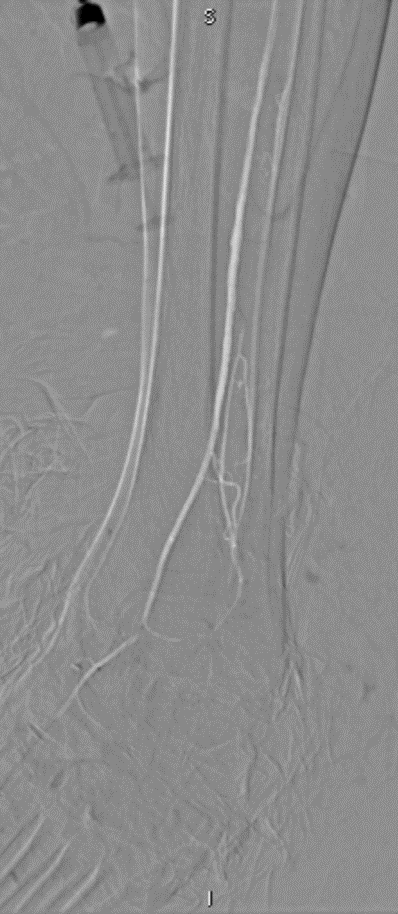

★ Case 3

左右滑动查看

★ Case 4

★ Case 5

Female,82 y

Severe claudication over 1 year in both extremities esp. in the left

DM over 10 years

CTA:SFA-PA long CTO

开通:以内膜下技术为主,逆穿是常用且有效的辅助手段。

预扩:充分预扩张至关重要,需逐级使用高压球囊,最终达到 6mm 直径,以获得足够的管腔。

支架植入:遵循“由远及近”原则,先放置远端 DES,再覆盖中段 VB,最后处理近端。利用 Eluvia 的可调节性优化重叠。

后扩:常规使用 6mm 高压球囊进行后扩张,确保支架充分贴壁和管腔获得。